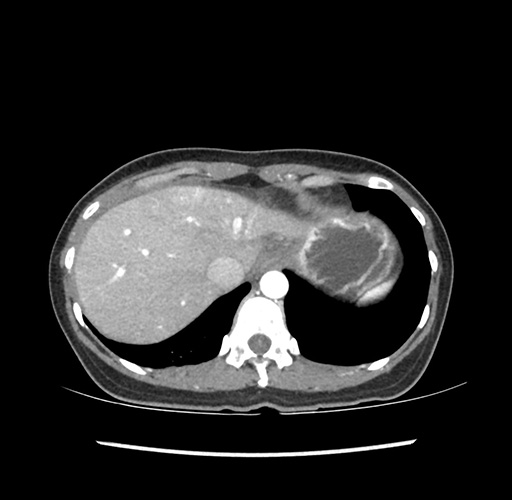

Imaging Analysis

Look through the patient's CT scan to identify any areas of concern for the necessary procedure.

Based on your CT findings, which issue(s) would give reason for "planned slowing down moment(s)" in this case?